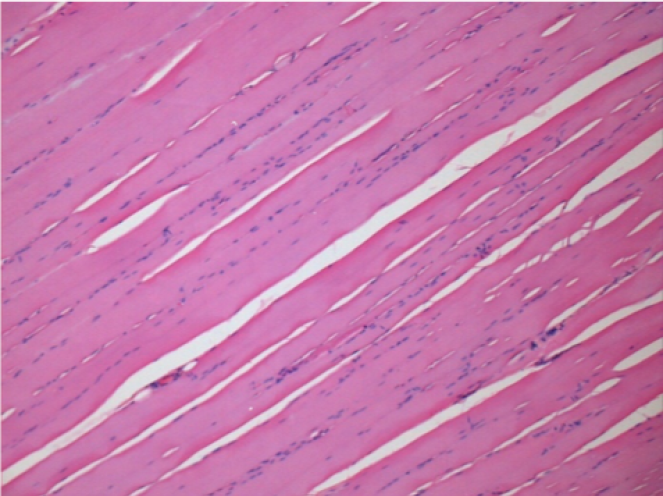

L:Pretibial-No treatment

7 months (D210)after Endopeel IM Injection 0.1ml in the right pretibial muscle.

Complete Restitutio ad integrum after 7 months

L :Control 50xD210